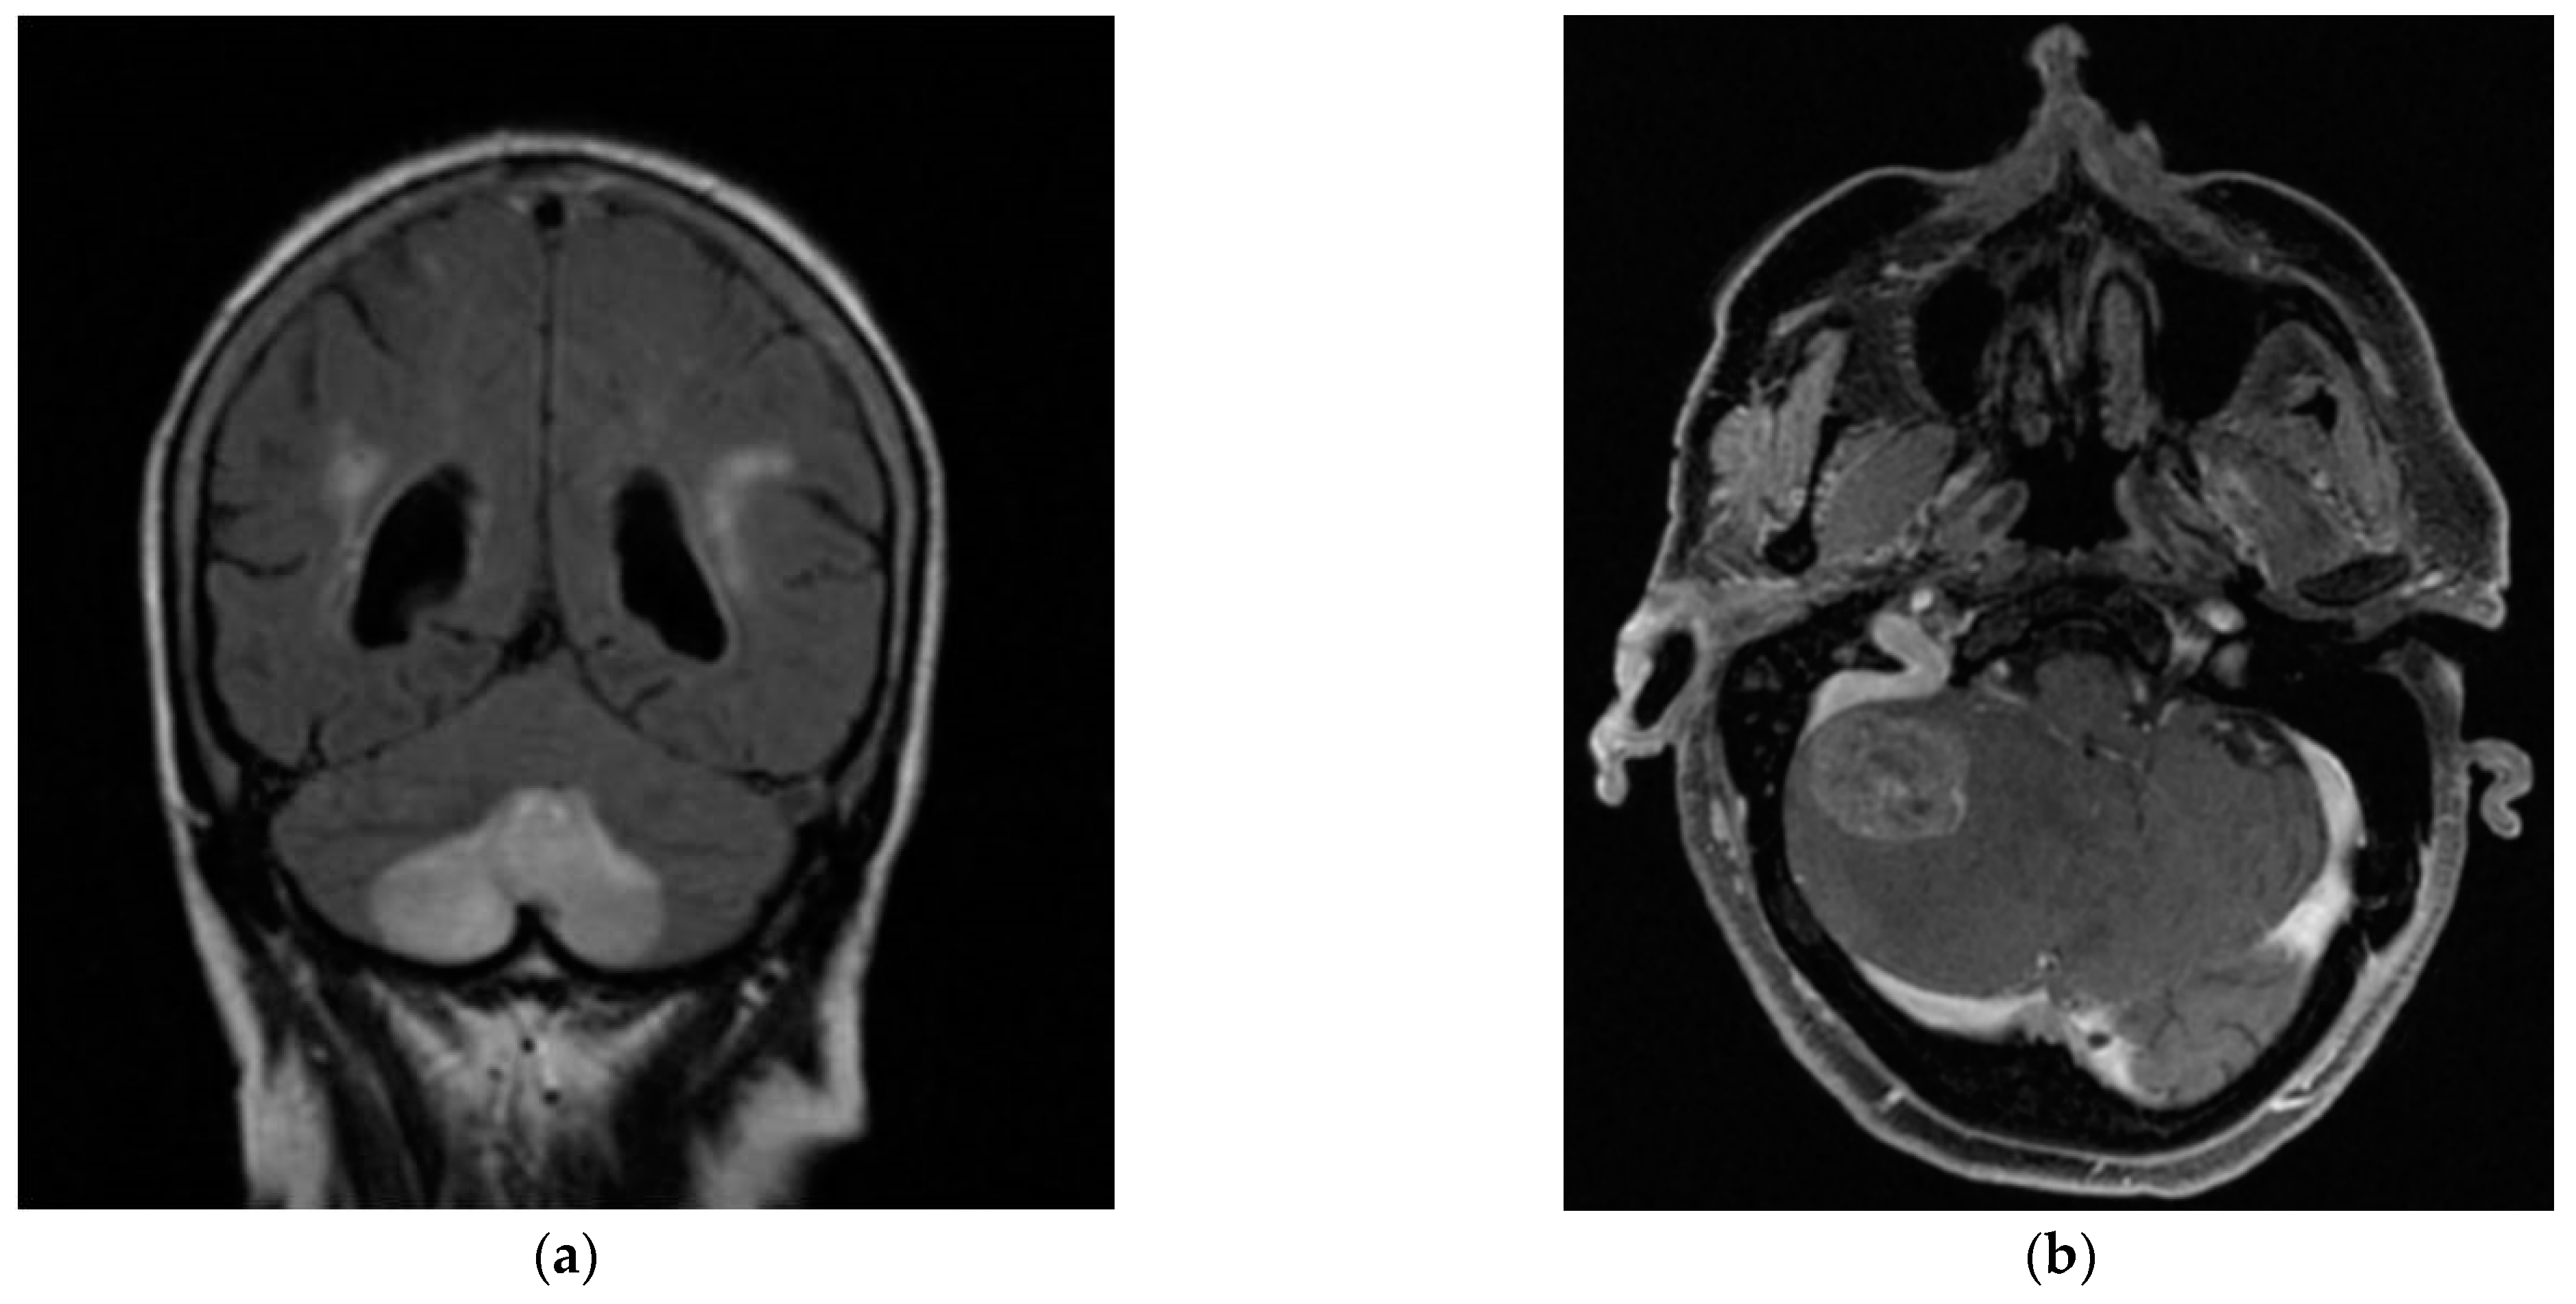

In Cohort B, 29 patients (64.4% of the total) were seen in the ENT ED, according to the previously described protocol. Of these, 44.8% were female, with a mean age of 67.07 years (SD 14.09) and a mean of 3.6 days of days from symptom onset to evaluation. 27.6% of the patients in the cohort presented a prior clinical history of BPPV (6.9% pc-BPPV and 10.3% hc-BPPV). One patient (3.4%) in Cohort B had mc-BPPV at the time of hc-BPPV-cu diagnosis, involving a combination of posterior canal and horizontal canal. In 75.9% of the cases treated in the ED, the hc-BPPV-cu was resolved with the first maneuver performed, the majority being Gufoni’s (69% of the cases). We found that 13.7% of the patients in the cohort required more than one maneuver to resolve their pathology, a change of maneuver being necessary in 10.3% of these at the next follow-up. In 3 patients in the cohort (10.3% of the total patients in Cohort B) the hc-BPPV-cu was not resolved despite repeated maneuvers, all of whom had a central cause identified on subsequent imaging (Figure 2)

Figure 2.

Bilateral posterior inferior cerebellar artery (PICA) infarction (a), in a patient with cardiovascular risk factors (arterial hypertension, atherosclerosis and diabetes mellitus). Metastasis in the right cerebellar hemisphere (b) associated with a personal history of metastatic colon cancer and headache and profuse vomiting.

Notably, hc-BPPV-cu was not resolved in 2 patients attending the OC and in 3 from the ED. All of these showed central pathology on subsequent MRI brain scans, thus mimicking hc-BPPV-cu, but presented with additional neurological symptoms. In the OC cohort, one patient with a hemipontine stroke (Figure 1) had associated cardiovascular risk factors (arterial hypertension and dyslipidemia) together with right-sided hearing loss and marked unsteadiness. The second patient with cerebellar atrophy, associated instability and a cerebellar pattern videonystagmogram and a left vestibular deficit of 28%. In the ED cohort, one patient had a stroke due to bilateral Posterior Inferior Cerebellar Artery (PICA), associated with cardiovascular risk factors (arterial hypertension, atherosclerosis and diabetes mellitus), unsteadiness and gait ataxia; another patient had dissection of the vertebral artery, associated with severe neck pain; the third patient was found to have metastasis in the cerebellar hemisphere, in the context of a personal history of metastatic colon cancer, headache and profuse positional vomiting (Figure 2).

The need to identify ‘atypical’ BPPV features and associated central features is appropriately highlighted in the three patients evaluated at the ED setting and the two patients evaluated at the OC, all of whom were found to a central disorder that mimicked a hc-BPPV-cu. The patient who suffered a bilateral PICA infarction had a strong history of cardiovascular risk factors (arterial hypertension, atherosclerosis and diabetes mellitus), raising our suspicion of a possible ischaemic aetiology [30], together with marked gait ataxia, less typical for BPPV. The degree of vestibulospinal involvement is an increasingly recognized factor for the differential diagnosis of central versus peripheral vestibulopathy, although it has only been confirmed in the context of the acute vestibular syndrome rather than BPPV [31]. However, the presence of ageotropic horizontal nystagmus has also been recognized as a hc-BPPV-cu mimic, as in the case of a unilateral large cerebellar infarct involving the nodulus [32]. In the case of the patient with a dissection of the vertebral artery in our cohort, the positional symptoms were associated with intense neck pain, not consistent with BPPV. In the case of the patient with metastasis in the right cerebellar hemisphere, the personal history of metastatic cancer, together with headache and profuse vomiting, classical symptoms of intracranial hypertension, were strong red flags that prompted further evaluation. In this patient, vomiting may be a reflex of central positional pathology, caused by the metastasis as a space occupying lesion. The cause of vomiting may be related to involvement of cerebellar and brainstem pathways necessary for the integration of vestibular and non-vestibular afferents relating to body position in space [29,33]. In these three cases, a cerebral MRI was performed following the criteria established for the suspicion of central pathology in BPPV [13].

Central pathology was located in cerebellum in three patients in our study. It involved a patient evaluated in OC, who presented cerebellar atrophy, and two patients from the ED, one of them with bilateral PICA infarction, and the other one with metastasis in the cerebellar hemisphere. Central positional nystagmus and vertigo had been previously explained by cerebellar or brainstem lesions around the fourth ventricle which may interrupt the vestibular nucleus-vestibulocerebellar loop as well as the cerebellar nodulus or uvula lesion. Specifically, apogeotropic nystagmus in these lesions may be explained by inhibition of the vestibulo-oculomotor system including the cerebellar flocculonodular lobe or vestibulo-cerebellum, through its connections with the otolith organs and with the vertical semicircular canals. These structures control the otolith-ocular reflexes and otolithic modulation of the semicircular canal-ocular reflexes [36]. Consequently, patients are often first misdiagnosed with hc-BPPV-cu due to apogeotropic nystagmus and positional vertigo [37], as reflected in our sample.